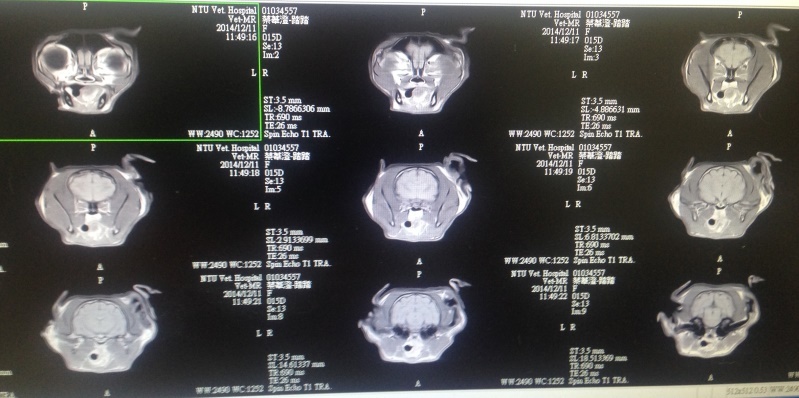

踏踏至台大就診,貓癲癇有自發性也有病因性,醫師建議可以接受核磁共振攝影檢查,排除是否是腦部腫瘤或者海馬體壞死等問題,以上兩者病情會惡化,若可以排除或者確定病因對後續控制是有效益,當然比較複雜性的病因有可能現階段醫療技術無法治療,因踏踏正值壯年,貓生還漫長,醫師是有建議在狀況好的時候,進行檢查確認,否則一但惡化可能身體經不起麻醉,同時麻醉一樣會有風險、打顯影也有過敏的可能,但機率極低,麻醉時會一併進行腦脊髓液採樣分析,踏踏看診中在醫師摸摸下還舒服的睡著....

103/12/11踏踏安排做核磁共振以及腦脊髓液採樣分析,發現病無先天上結構異常,目前也沒有後天的腦部病變,血檢排除離子不平衡、中毒等狀況,醫師研判應該是不明原因自發性癲癇,有可能是遺傳基因的病變,有些在中年後腦細胞衰快速衰退,到時後腦部磁振造影才可能看出明顯的差異,目前腦狀況正常,海馬體也沒有萎縮,接下來就是需持續用藥物控制、追蹤,很慶幸至少在這些日子中,踏踏得到極好的控制沒有發病過,現在也確定並不是腦腫瘤病變,也代表踏踏只要按時服藥現階段與正常貓無異,還有很多幸福快樂的日子,每個月定期回診追蹤血檢數值、監測癲癇藥物反應,也從瘦巴乾扁變成圓潤可愛許多...